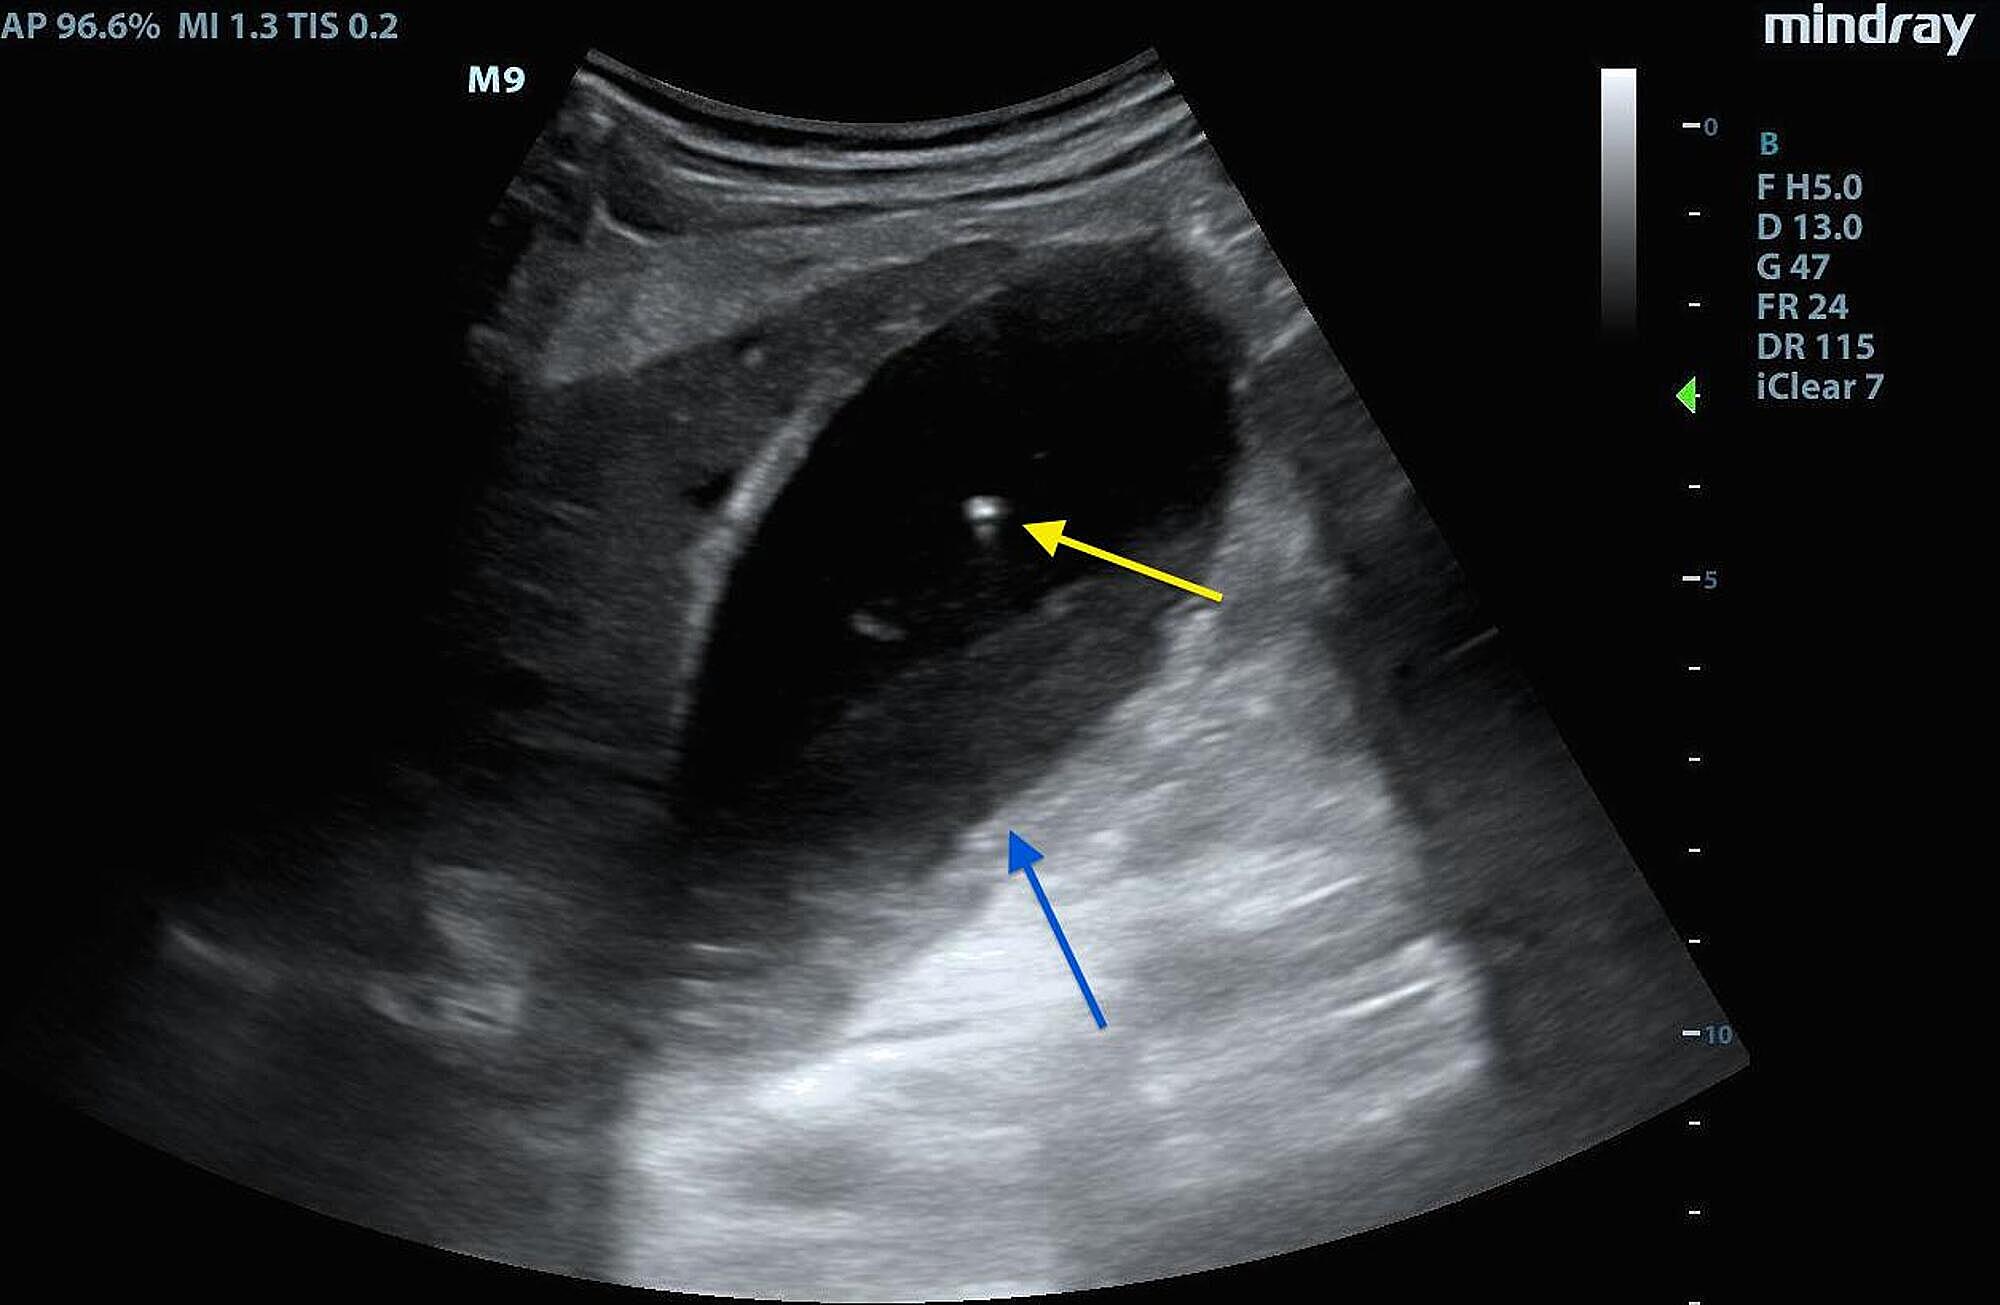

Air bubbles are visible inside the bladder (b), strictly adherent to What Causes Air Bubbles In Bladder Air in the bladder, also known as pneumaturia, is a rare condition that occurs when air accumulates in the bladder. Urine usually comes out with a few bubbles in it purely as a result of air bubbles being formed after it hits the toilet water. In the hospital setting, by far the most common is the placement of an. This. What Causes Air Bubbles In Bladder.

Air bubble (arrow) in the urinary bladder. Download Scientific Diagram What Causes Air Bubbles In Bladder The abnormal communication between the bowel. The most common cause of pneumaturia is an enterovesical fistula. Air in the bladder, also known as pneumaturia, is a rare condition that occurs when air accumulates in the bladder. “the most common cause of air in the bladder on imaging is from instrumentation [bladder viewing], a recent cystoscopy or foley catheter,” says dana. What Causes Air Bubbles In Bladder.